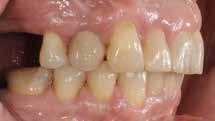

I samråd med patienten og egen tandlæge* afstemmes forventningerne, inden der bestilles refinement alignere. Nivelleringen af alle tænder i tandbuerne, smilelinje og -kurve samt den bukko-lingvale position af incisiverne foretages og efterfølges af retainers lingvalt på over- og underkæbeincisiver (Fig. 3 A-D). Hele behandlingen udføres under løbende kommunikation med patient og egen tandlæge*, der udfører den efterfølgende rekonstruktion med direkte plast (Fig. 4 A-D). Behandlingsvarigheden har været to år og to måneder, hvor ortodontien har forløbet over 21 måneder. Der har været anvendt et første sæt på 66 alignere samt yderligere to sæt med ni refinement alignere. Tandblegning og direkte plastrekonstruktion er udført af egen tandlæge* (Fig. 5 A-F).

Fig. 5. A, B. Smil og kæbeforhold før og efter. Et bredere smil med korrektion af de laterale mørke rum. C-F. Harmonisk hældning af overkæbe- og underkæbeincisiver, rekonstruktion af den tabte tandsubstans efter nivellering af gingivaniveau og optimal bukko-lingval placering til direkte plastbehandling.

5. A, B. Smile and jaw relationships before and after. A wider smile with correction of the lateral dark spaces. C-F. Harmonious inclination of the upper and lower jaw incisors, reconstruction of the lost tooth substance after leveling the gingival level, and optimal bucco-lingual positioning for direct plastic treatment.